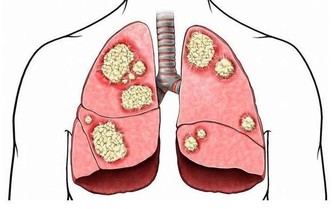

花生當中含有非常多的營養價值,並且花生當中含有豐富的核黃素,硫胺素,尼克酸等多種維生素,礦物質含量也比較多,特別是含有生體所必需要的氨基酸,

從中醫的角度上來講,入脾,肺兩經,能夠幫助調理營養不良,燥咳少痰,食少體弱,產婦乳少,皮膚紫斑,咯血,大便燥結等等。